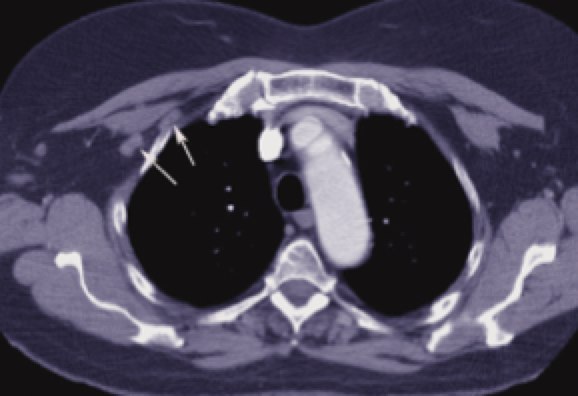

Fields and treatment volumes

CT simulation is very useful to precisely delineate the target volumes. The IMN vessels are found within the first 3 intercostal spaces and are the region where the IM nodes are at highest risk. Using the IM vessels. The depth of the Level III axillary and supraclavicular nodes is also variable. The depth can be easily determined from CT imaging. Contouring these nodes in the treatment planning system can insure they are adequately treated. Studies of treatment planned patients using a 6 MV anterior oblique supraclavicular field prescribed to a depth of 3 cm can significantly underdose nodes in patients who are overweight or obese.